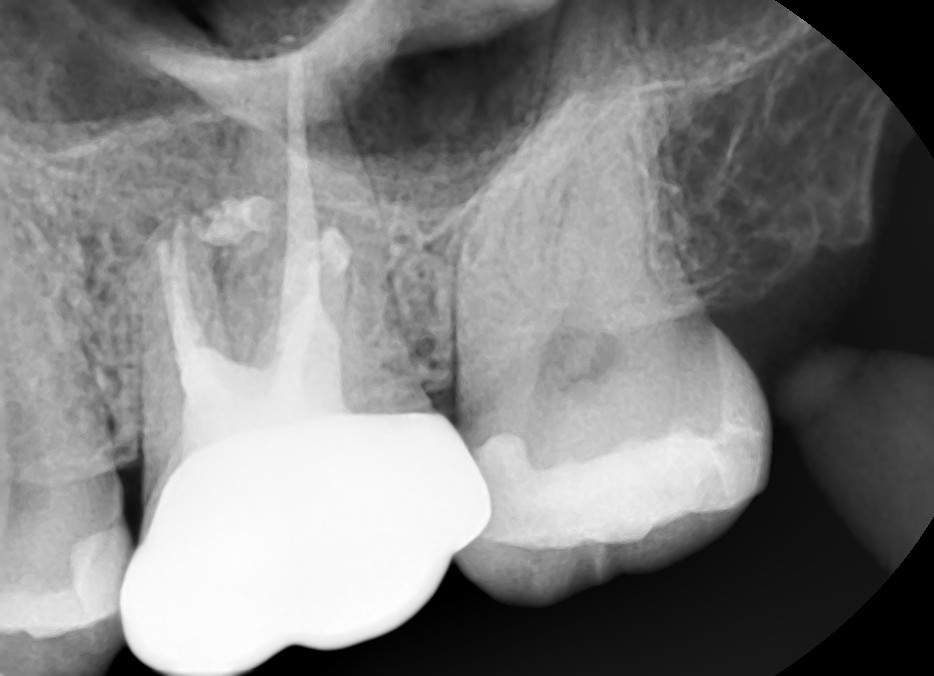

Case #1

치료 전